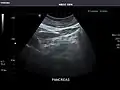

Pancreas

Pancreas: Visualized portions unremarkable.